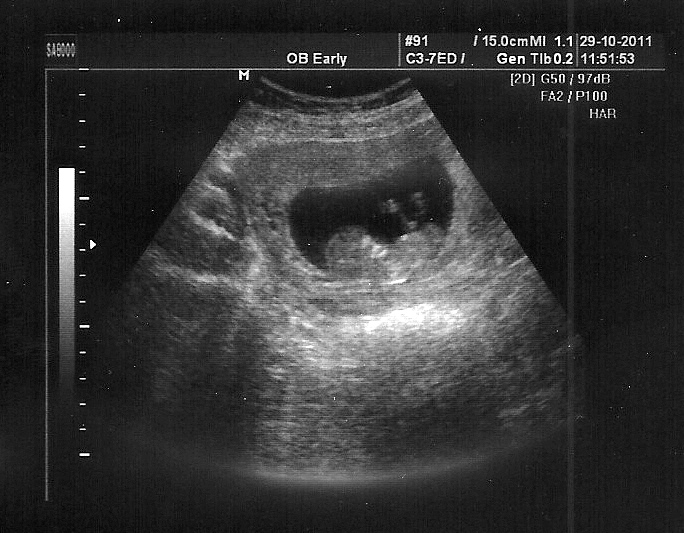

29.10.2011

Cosi se tu líhne...

...ale zatím je to tajný, neb ještě nemáme ani 3 měsíce.

...a bude to Jáchym nebo Barborka?;)

(Ultrazvuk u Vendy)